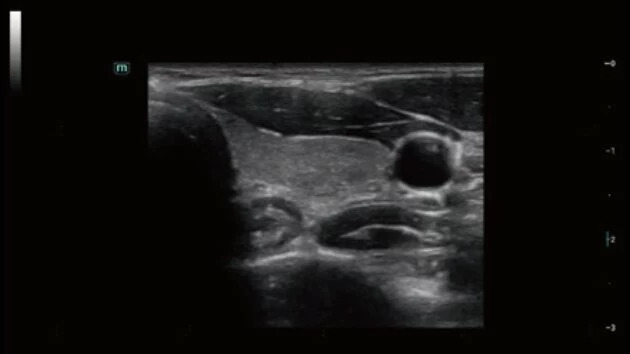

Ультразвуковой аппарат Mindray Consona N7 принадлежит к категории устройств экспертного класса и предназначен для проведения широкого спектра общей диагностики. Благодаря высокому уровню визуализации, он активно применяется в кардиологии, а также для гинекологических исследований.

Mindray Consona N7 представляет собой передовую диагностическую систему, созданную для ежедневного клинического использования с акцентом на высокое качество визуализации.

• Широкий спектр клинических исследований

• Расширенные возможности визуализации различных органов и тканей